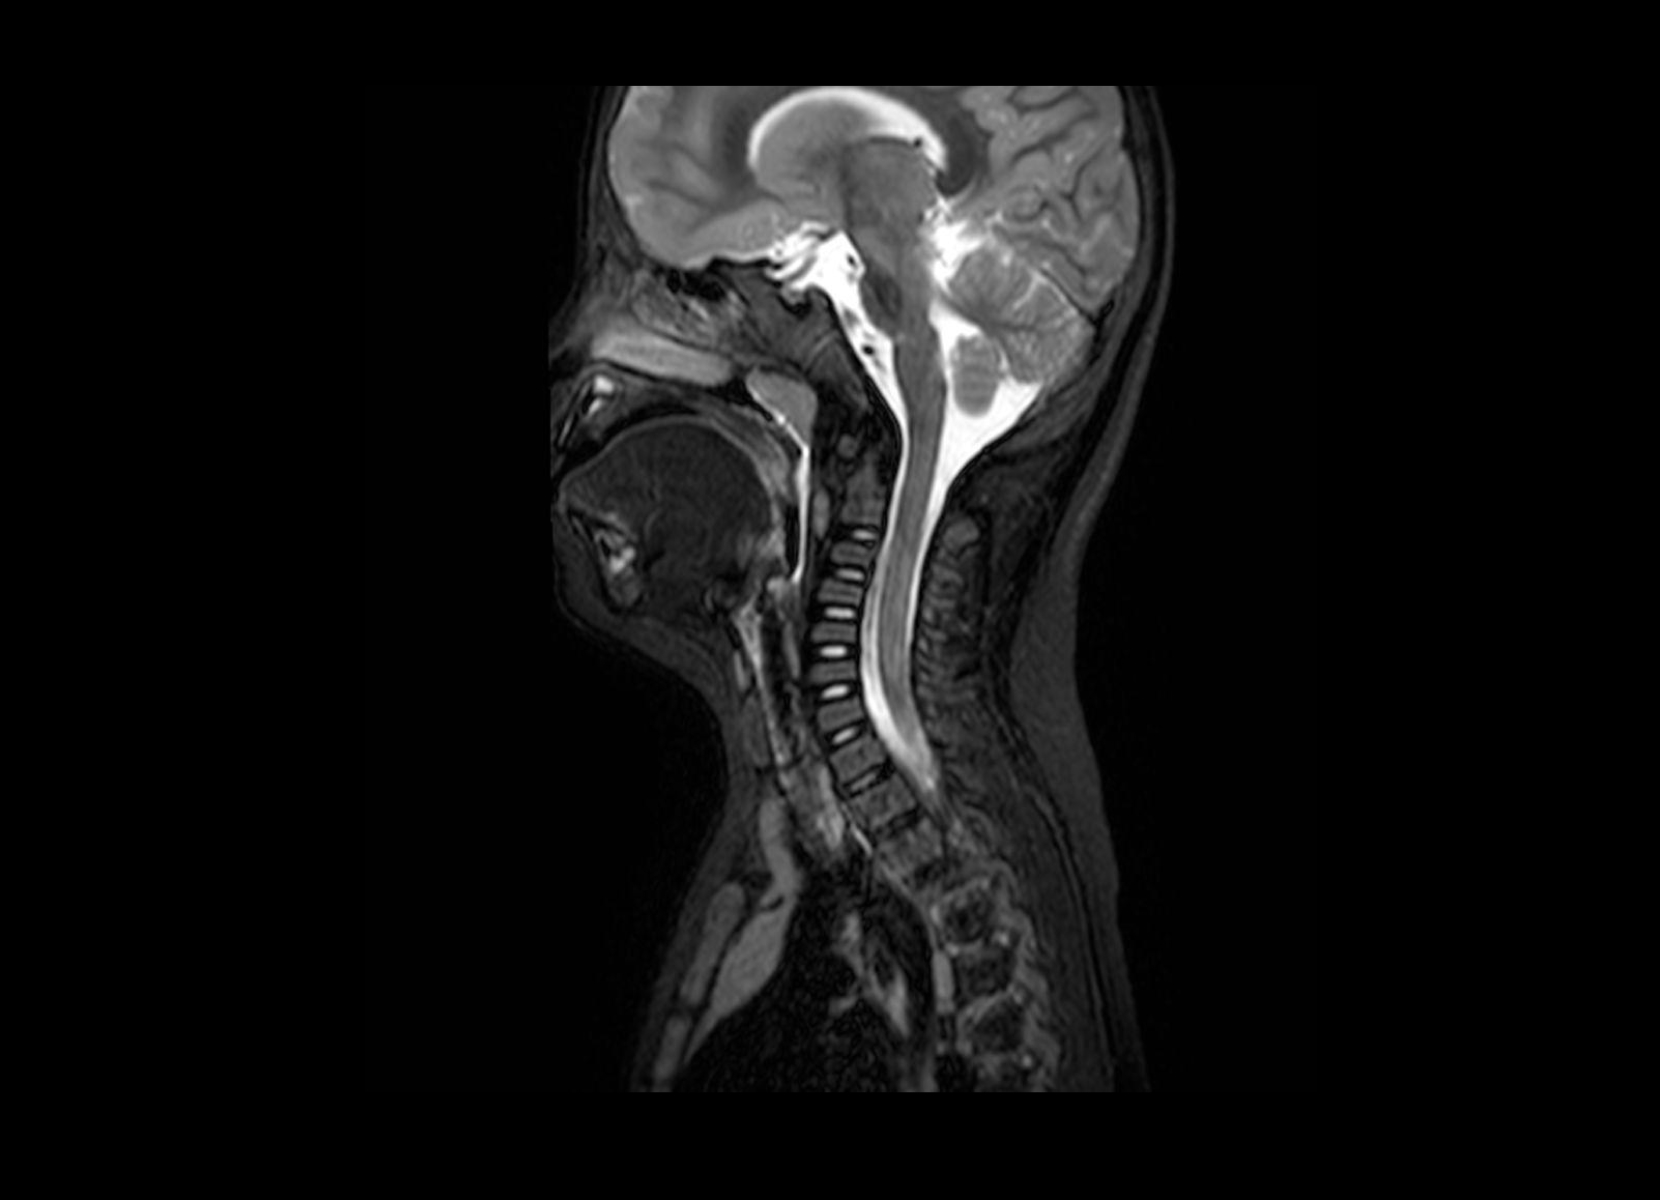

Conventional

STIR

SubtleSYNTH™

(Synthesized STIR)™

Trauma

GE 1.5T

C-spine